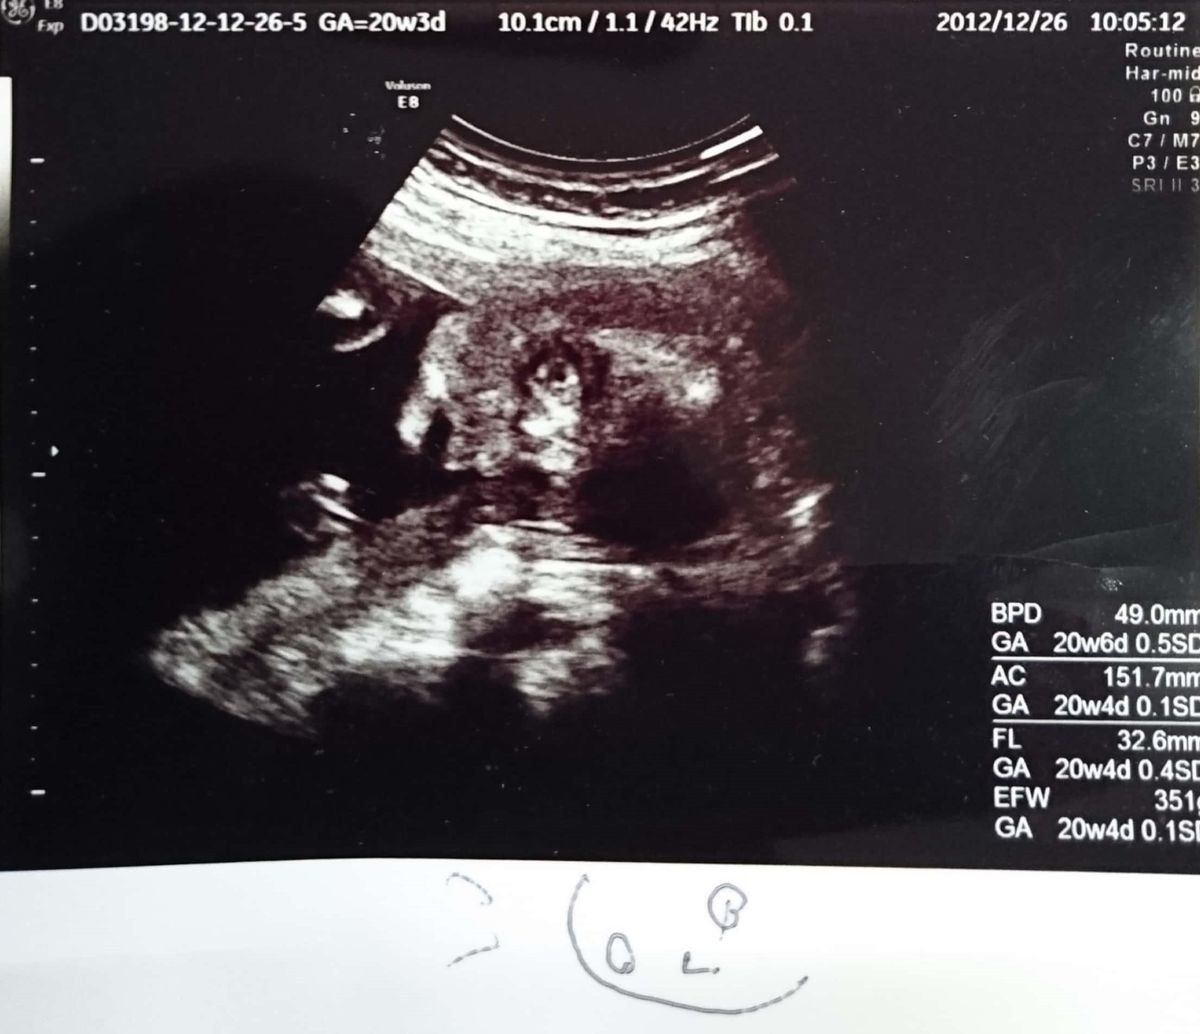

妊娠20週のエコー写真 ちょっとホラー並みのエコー写真でコンニチワ

FL(太ももの骨の長さ):32.6mm

エコー写真ではいつも背中を向けていた胎児が、ついにこっちを向きました。すると、ちょっとしたホラーのような写真に…。写真下の絵は、先生の手書きの説明です。この頃になると、全長を測るのではなく、大腿骨長(太ももの骨の長さ)を測り、大きさの目安にすると先生に説明されました。この時に男の子のシンボルがしっかり映り、性別もほぼ確定しました。つわりもようやくなくなりました。